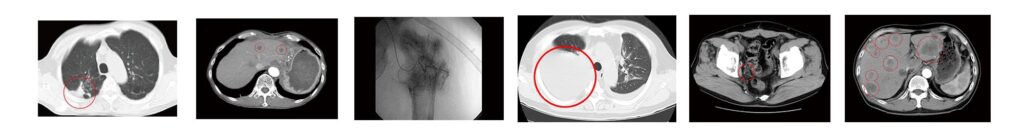

✅ CT・PET・MRI画像、各種診断資料対応

標準治療が難しいと説明を受けた方々の治療記録です

根治手術後、5年を経て発症した肝ぞう転移…

治療記録を読む ››数年前から尿の出が悪く、検査を受けると…

治療記録を読む ››発病の1年前から自覚していた腹部の違和感…

治療記録を読む ››治療6ヶ月後、胸水貯留と腫瘍マーカーが…

治療記録を読む ››61歳女性/乳がん手術後に多発性骨転移…

治療記録を読む ››41歳女性:子宮頸がん再発しリンパ節に移転…

治療記録を読む ››54歳女性/卵巣がん術後に局所再発。腫瘍は…

治療記録を読む ››64歳男性:大腸がん手術後に多発肝転移…